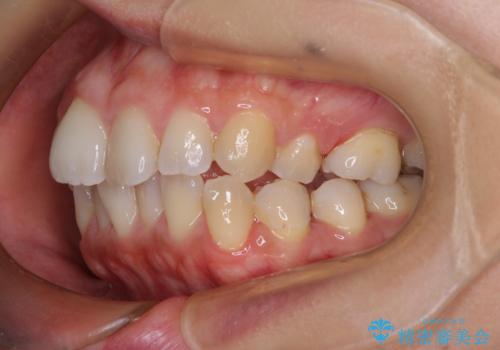

前歯のデコボコを改善 インビザラインの矯正治療

- 前歯のデコボコを治したいとのことで来院された患者様です。

上下顎ともに歯列全体の後方移動とIPR(歯と歯の間を削る)によってデコボコが解消するように設計し、インビザラインにより治療を行うこととしました。